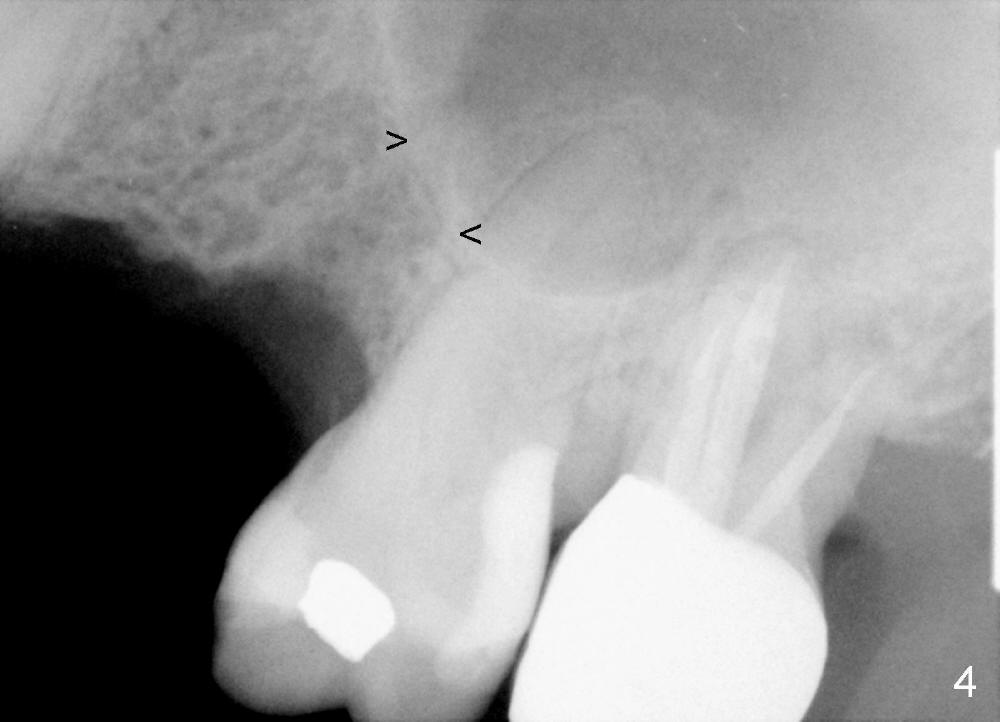

The anterior retainer is kept as a crown at #11 (Fig.2: C), whereas the residual root at the site of #13 is extracted with apical perforation (Fig.3 ^). It is confirmed by Fig.4 (<). To close the perforation, an osteotomy is initiated on the palatal wall of the socket with a 2 mm osteotome (Fig.5 insert: circle). As the osteotomy is being enlarged by a 3 mm osteotome, the bone between the original socket and the osteotomy is being pushed buccally. The former is being closed (Fig.5). The osteotomy is finished with combination of osteotomes and reamers. Fig.6 shows that a 5x14 mm tap is inserted at the site of #13 and that the sinus floor is lifted. In fact the sinus membrane is partially torn at the osteotomy, which is repaired by insertion of Colla-form Dressing (Impladent), followed by autogenous bone (harvested from reamers) mixed with Osteogen (Impladent). A 5x14 mm implant is placed at the site of #13 with insertion torque more than 60 Ncm (Fig.7: I). An incision is made at the site of #12 to start osteotomy with insertion of a parallel pin (Fig.7 P). A 3 mm reamer is kept in place for position confirmation (Fig.8 R). Due to ridge atrophy (Fig.2 arrowheads), a much smaller, but longer implant is placed at the site of #12 (Fig.9: 4x17 mm). The autogenous bone harvested from #12 osteotomy is placed in the buccal gap of #13, followed by insertion of Colla-form Dressing (Fig.10 M). To protect the membrane, a short abutment (4x3 mm) is temporarily placed (Fig.9,10 A) and perio dressing (Fig.9 D) is applied around the abutment and the interproximal areas of the neighboring teeth. Usually perio dressing dislodges around 1 week postop, particularly for a large edentulous space. In this case, the dressing is quite stable 11 days postop: the abutment (Fig.11 A) appears to contribute to retention of the dressing (D).